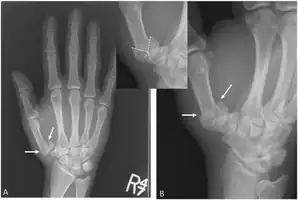

'Y-shaped' Rolanda fracture

The cause is generally a force along the long axis of the thumb, such as during a fight.[3][4] Diagnosis is by medical imaging; such as X-ray, CT scan, or MRI.[3] It results in at least three bone fragments, which often form a T- or Y-shaped pattern.[3][4] It differs from a Bennett fracture which only results in two bone fragments.[4]